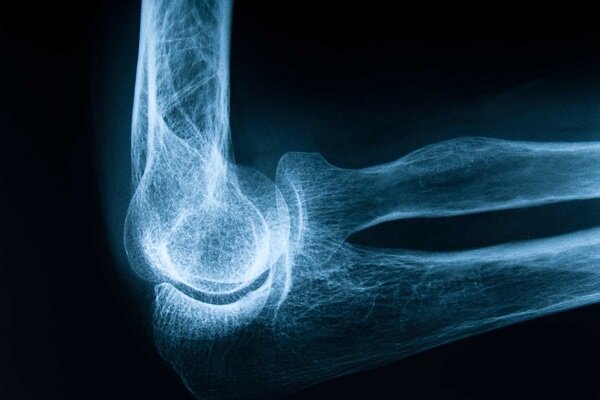

انتخابتو، پوکی استخوان یا پوکی استخوان یک بیماری مزمن و پیشرونده است که با کاهش تراکم و کیفیت بافت استخوانی، ساختار استخوان را شکننده و آسیب پذیر می کند. این بیماری اغلب بدون علائم بالینی خاص پیشرفت می کند و ممکن است فرد تا زمانی که شکستگی رخ ندهد از وجود آن بی خبر باشد. شکستگی های ناشی از پوکی استخوان، به ویژه در ناحیه لگن، ستون فقرات و مچ دست، می تواند منجر به درد مزمن، محدودیت حرکت، بستری شدن طولانی مدت در بیمارستان و حتی افزایش خطر مرگ در سالمندان شود و بنابراین پوکی استخوان نه تنها یک مشکل استخوانی بلکه یک مشکل جدی برای سلامت عمومی است.

تشخیص زودهنگام پوکی استخوان با اندازه گیری تراکم استخوان با روش DXA.جذب این آزمایش با اندازه گیری تراکم استخوان در نواحی حساس مانند لگن و ستون فقرات خطر شکستگی را پیش بینی می کند و طبق توصیه های بین المللی، زنان بالای 50 سال، مردان بالای 70 سال و افراد دارای عوامل خطر باید به طور مرتب غربالگری شوند و سابقه خانوادگی، استفاده از برخی داروها و بررسی بیماری های زمینه ای در ارزیابی خطر فردی مهم است.